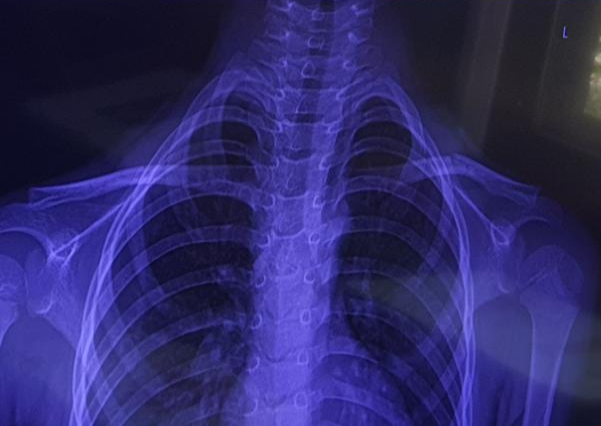

병원에 가서 엑스레이를 찍고 검사한 결과

역시나 쇄골 골절이었습니다.

위에 있는 저희 아이의 엑스레이 사진에서

쇄골뼈 중간이 부러진 것을 보실 수 있습니다.

정말 말 그대로 뼈가 '똑' 하고 부러진 것이

정확하고 선명하게 보이네요.